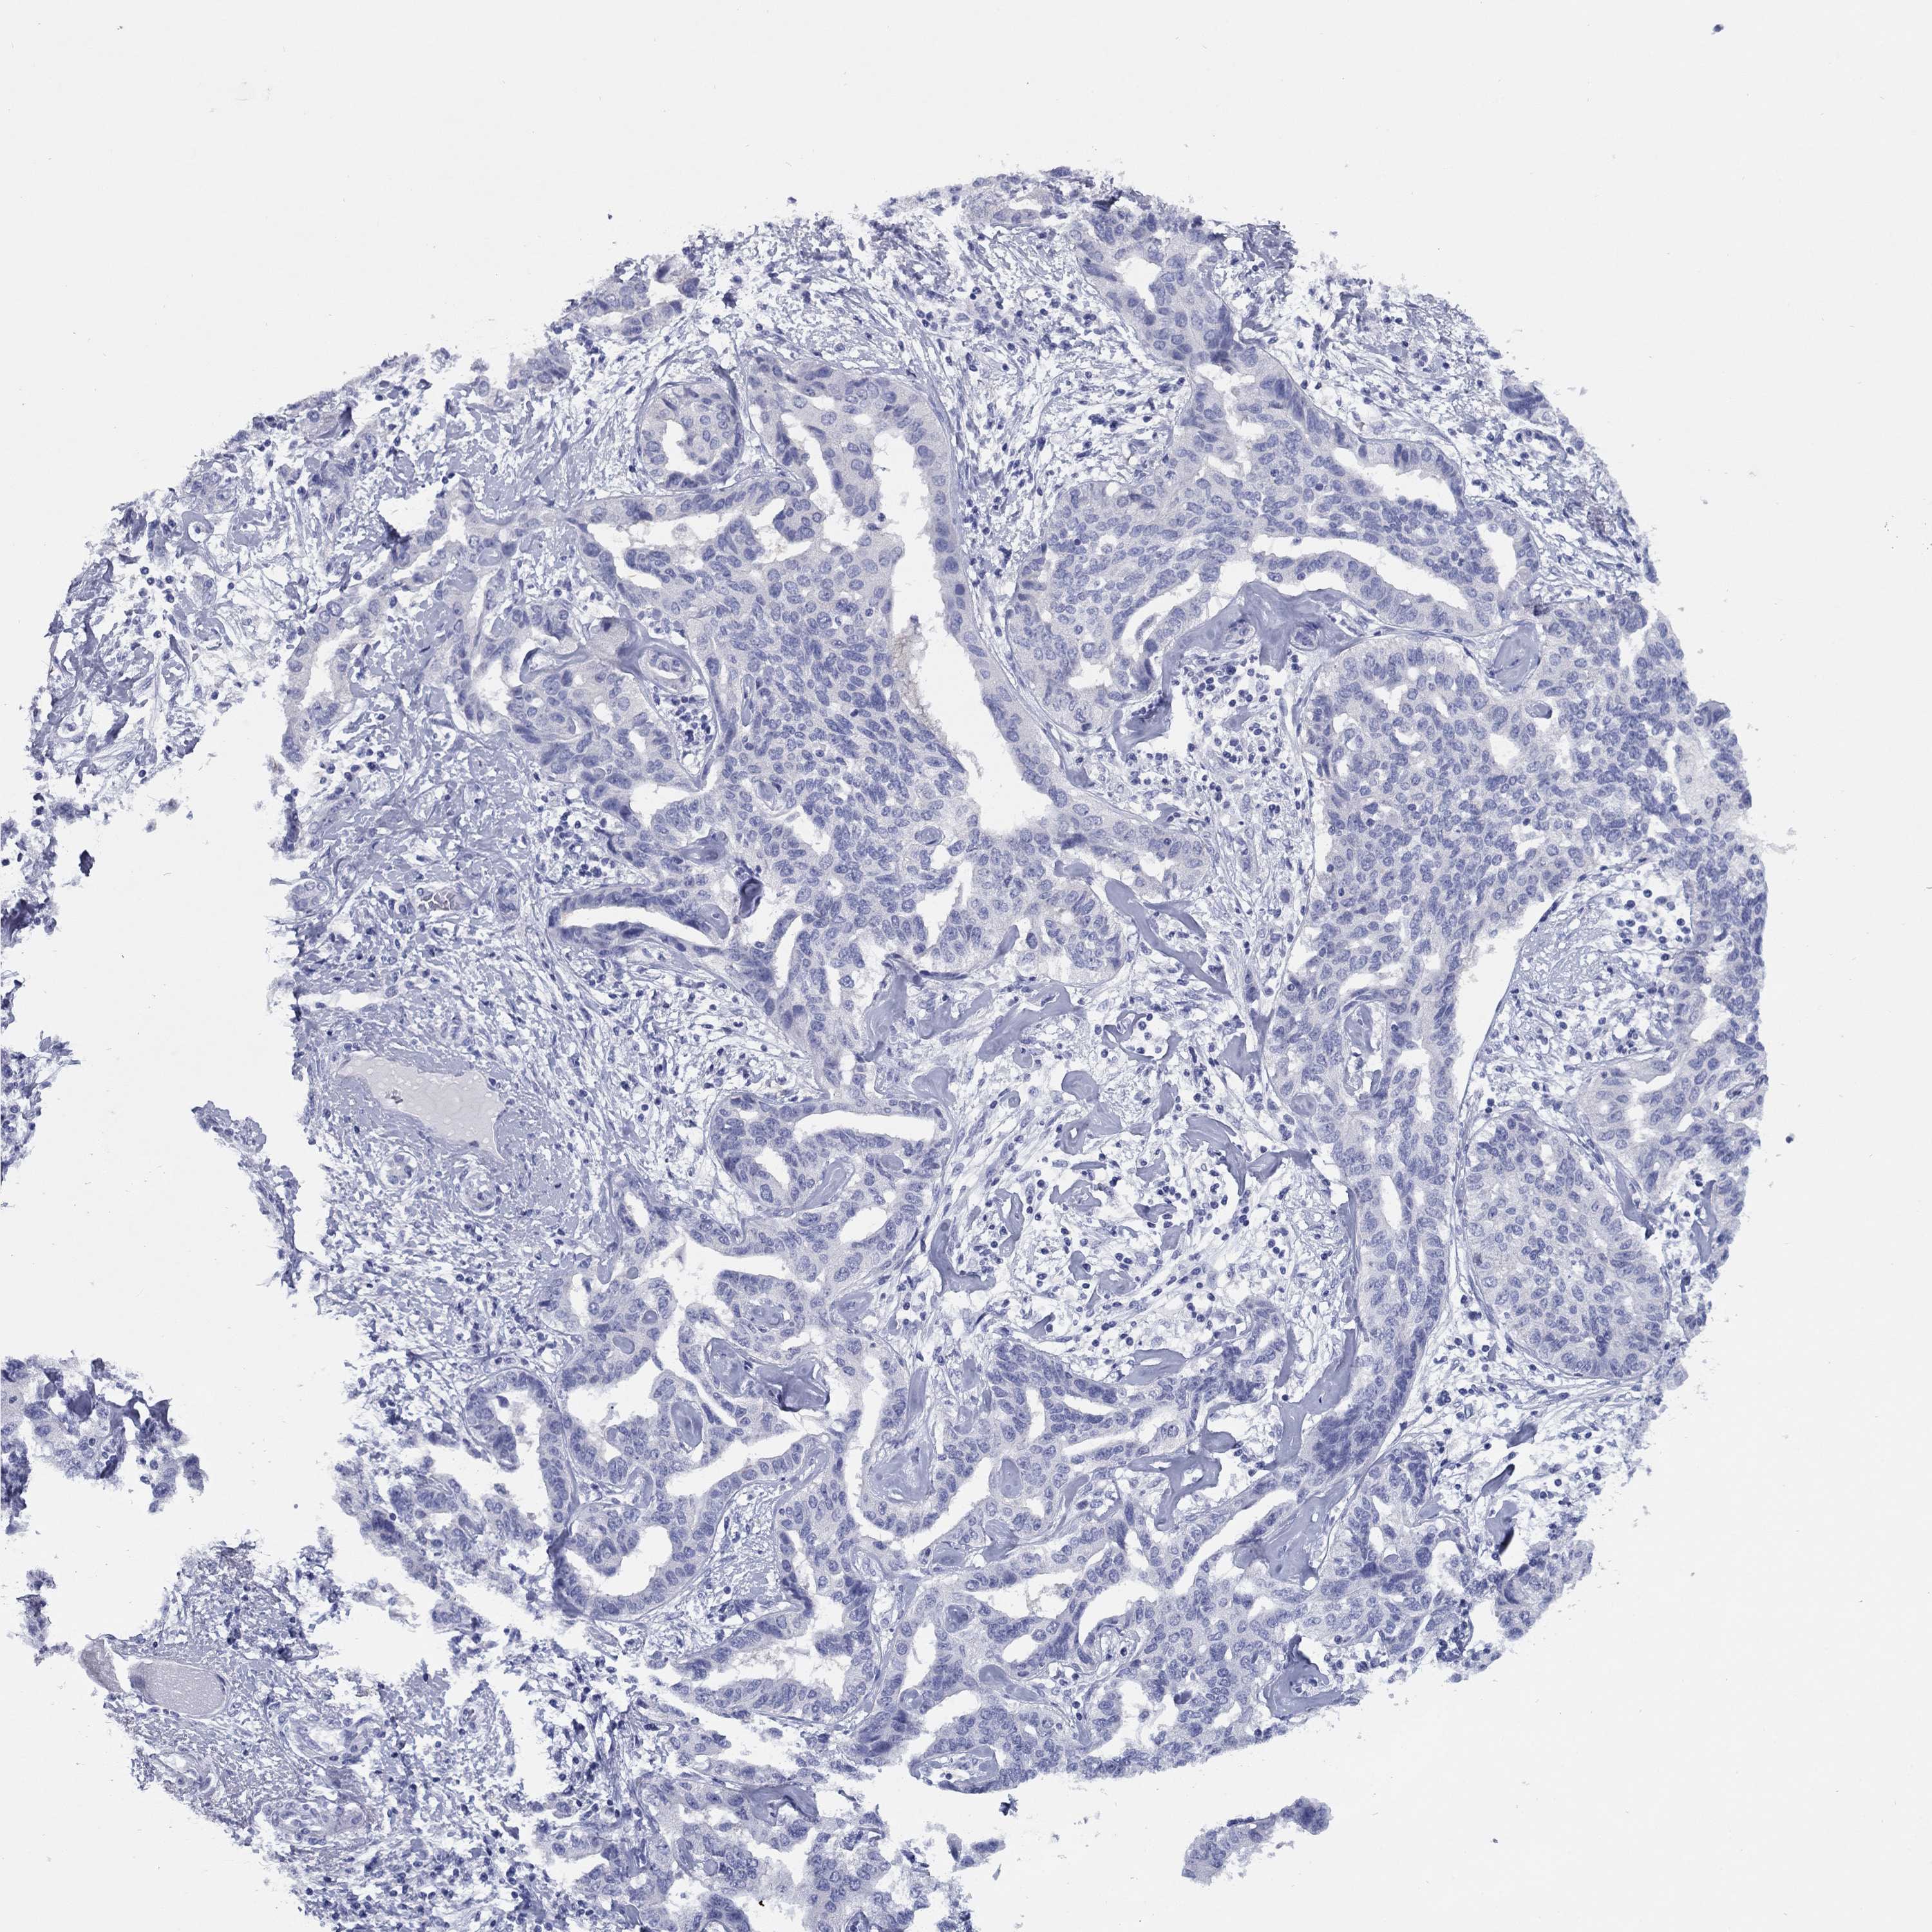

LIVER CANCER - Protein expressioni

A mouse-over function shows sample information and annotation data. Click on an image to view it in a full screen mode. Samples can be filtered based on level of antibody staining by selecting one or several of the following categories: high, medium, low and not detected. The assay and annotation is described here.

Note that samples used for immunohistochemistry by the Human Protein Atlas do not correspond to samples in the TCGA dataset.

Antibody stainingi

Antibody staining in the annotated cell types in the current human tissue is reported as not detected, low, medium, or high, based on conventional immunohistochemistry profiling in selected tissues. This score is based on the combination of the staining intensity and fraction of stained cells.

Each image is clickable and will lead to virtual microscopy that enables deeper exploration of all samples and also displays staining intensity scores, fraction scores and subcellular localization as well as patient and tissue information for each sample.

Antibody HPA058269

Antibody HPA064007

Staining

High

Medium

Low

Not detected

Intensity

Strong

Moderate

Weak

Negative

Quantity

>75%

75%-25%

<25%

None

Location

Nuclear

Cytoplasmic/membranous

Cytoplasmic/membranous,nuclear

Carcinoma, Hepatocellular, NOS

Cholangiocarcinoma